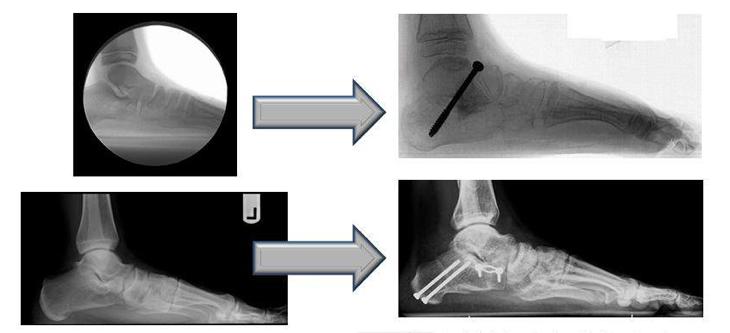

但如果小朋友10岁以后扁平足还没有得到明显改善,而且行走时有明显不适或疼痛感,我们建议可能要进行一些手术干预,手术方法有肌腱移位、韧带紧缩等软组织手术,也有跗间关节融合、跗骨截骨等骨性手术,目前多倾向于软组织和骨性手术联合应用,这样效果更好。